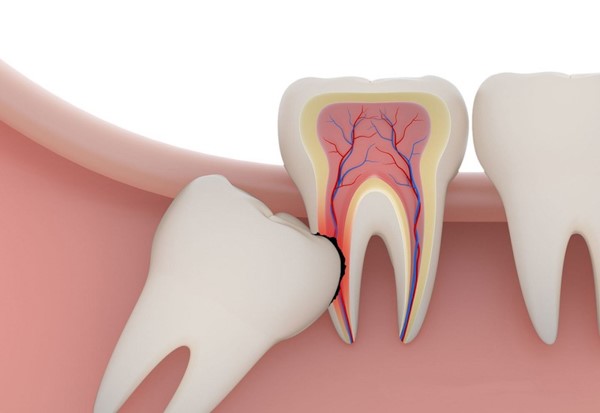

- Gây đau nhức: Mọc lệch, mọc ngầm sẽ gây ra áp lực lên các răng kế cận, gây đau nhức, thậm chí là nhiễm trùng.

- Răng mọc lệch, mọc ngầm: Gây ảnh hưởng đến các răng kế cận, gây đau nhức, viêm nướu, khó vệ sinh răng miệng.

- Răng mọc ngầm gây áp lực: Lên các răng khác, làm cho các răng này bị dịch chuyển, ảnh hưởng đến khớp cắn.

Vấn đề sâu, viêm của răng

Nếu răng số 8 bị sâu hoặc viêm, quá trình nhổ răng sẽ phức tạp hơn và đòi hỏi thêm các liệu pháp điều trị trước khi thực hiện quá trình nhổ. Điều này có thể làm tăng chi phí tổng cộng cho việc nhổ răng.

Vấn đề răng mọc ngầm

Răng số 8 mọc ngầm dưới nướu cũng là một yếu tố ảnh hưởng đến chi phí nhổ răng. Việc phải thực hiện phẫu thuật để lấy răng mọc ngầm có thể làm tăng chi phí và đòi hỏi thời gian và công sức lớn hơn từ phía nha sĩ.